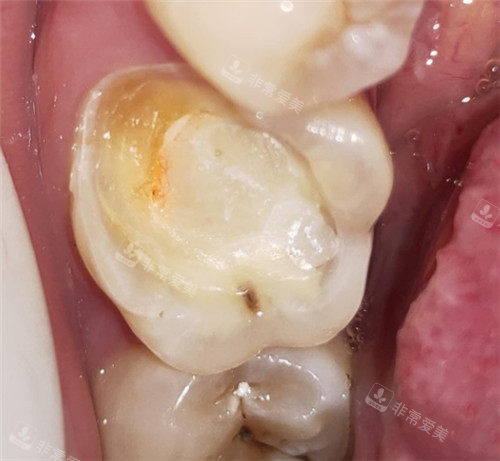

牙齿龋坏清理图

三、基础治疗结果好

该口腔机构在基础治疗方面表现出色。无论是常见的补牙、拔牙、洗牙,还是根管治疗等项目,都有着很高的治疗水平。以洗牙为例,医生会根据患者的牙齿情况选择合适的洗牙方式,在洗牙过程中能够有效地去除牙齿表面的牙结石、菌斑和色素,让牙齿修养洁净和健康。而且,洗牙后还会为患者提供正确的口腔护理建议,帮助患者保持口腔卫生。